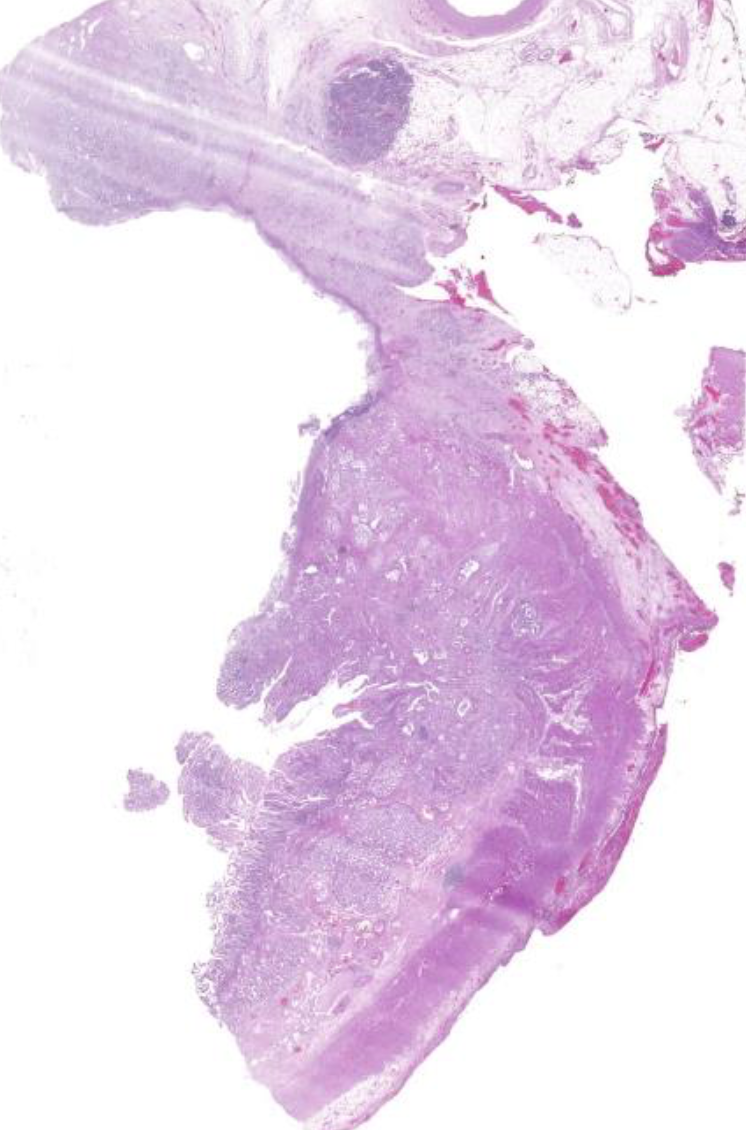

Diagnose?

Pleomorphes Speicheldrüsenadenom = BENIGNE

80% in der Parotis -> nicht destruktiv, nicht invasiv, nur verdrängend

v.a .Parotis, benigne, aufgebaut aus bindegewebiger Kapsel und epithelialen und mesenchymalen Gewebe (v.a. Knorpelgewebe)